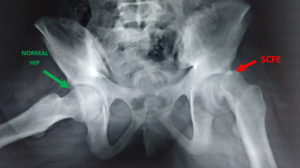

Slipped capital femoral epiphysis (SCFE)

In SCFE, the head, or “ball,” of the thigh bone (the femoral head) slips off the neck of the thigh bone. This condition causes the hip joint to become painful and stiff. The patient may be limping with pain or unable to walk. It is a rare condition which is seen only in 2 persons out of 1 lakh population.

Diagnosis of SCFE

SCFE can be diagnosed with medical history, physical examination and X-rays. In most cases it does not need CT scan or MRI scan to diagnose it. Once the diagnosis of SCFE is made, the child is not allowed to bear weight on the hip, in order to prevent the head of the femur from slipping further off of the thigh bone.